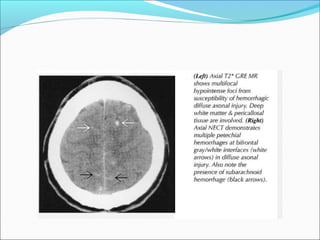

DIFFUSE AXONAL INJURYDIFFUSE AXONAL INJURY

ļ‚—Rarely detected on CT ( 20% of DAI lesions are

hemorrhagic)

ļ‚—MRI: T1, T2, T2 GRE, DWI

DAI

ļ‚—Due to acceleration/deceleration to whtie matter +

hypoxia

ļ‚—Patients have severe LOC at impact

ļ‚—Grade 1: axonal damage in WM only -67%

ļ‚—Grade 2: WM + corpus callosum (posterior > anterior)

– 21%

ļ‚—Grade 3: WM + CC + brainstem